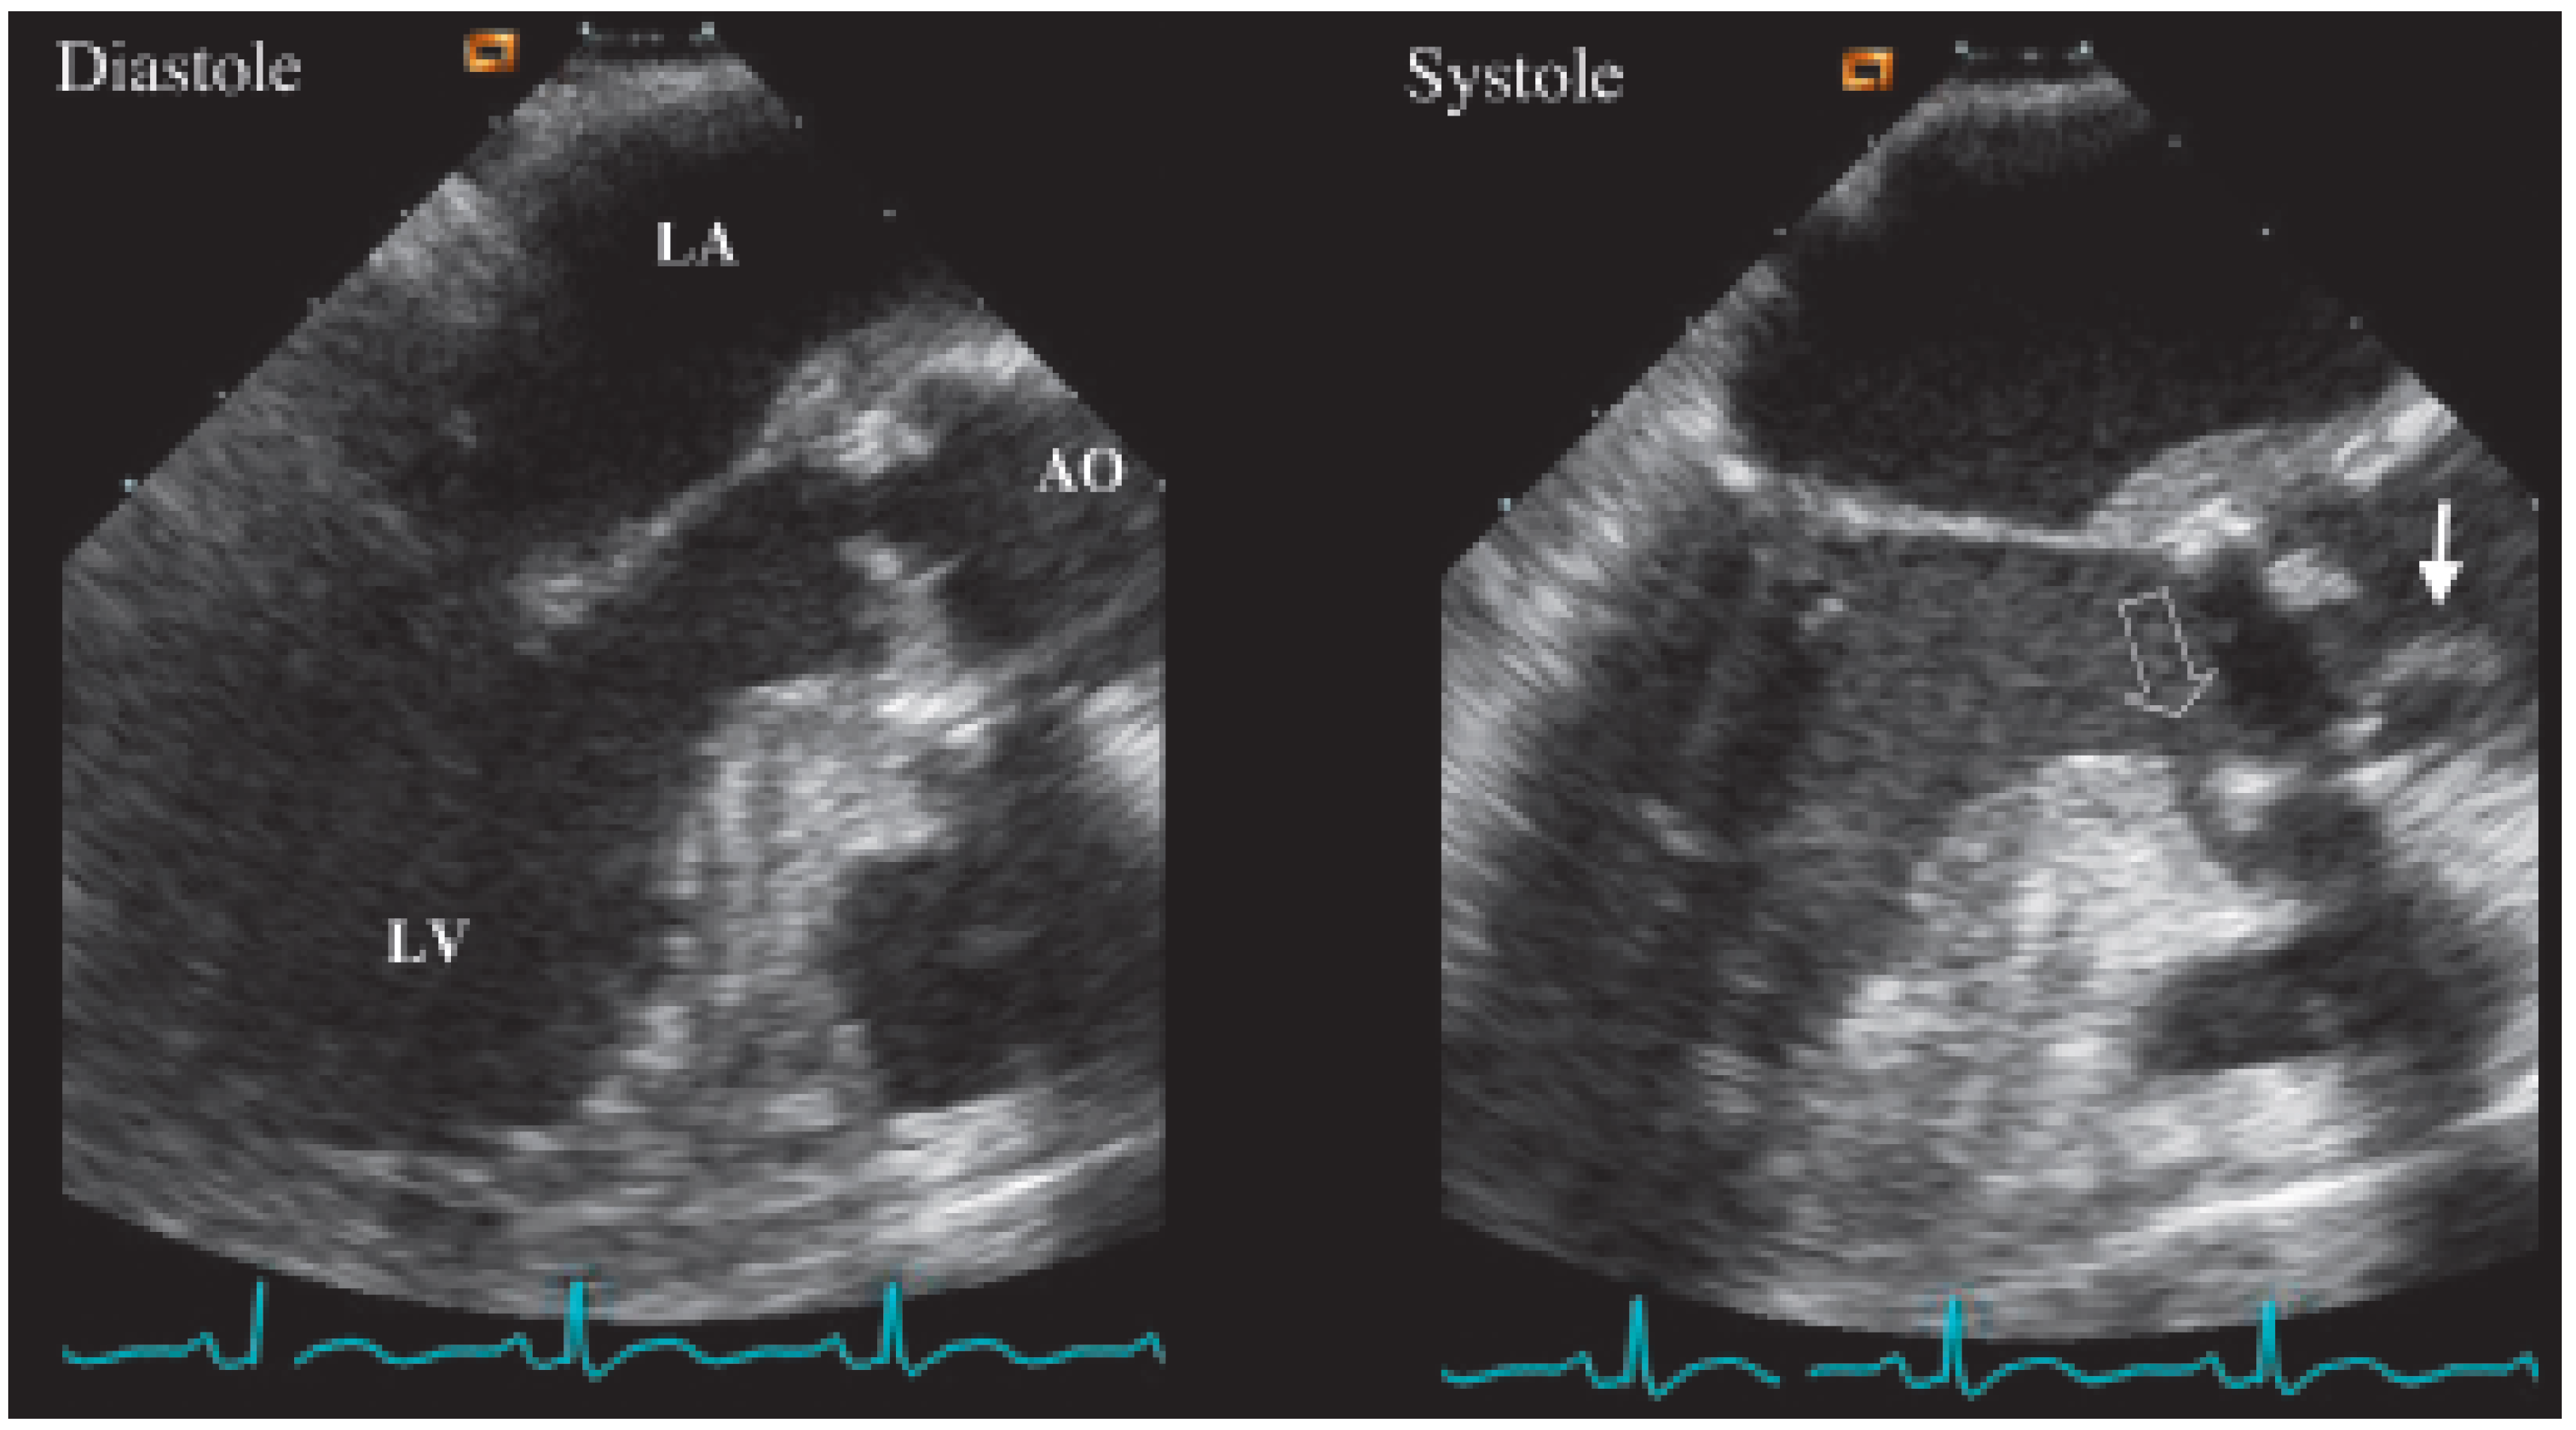

Transthoracic echocardiography was performed with only apical views available (Figure 1). It demonstrated abnormal motion of the prosthesis annulus but only a mild aortic insufficiency. Neither vegetations nor abscess were visualised. As the probability of prosthetic endocarditis was high, a transoesophageal echocardiography (Figure 2 and Figure 3) was organised immediately afterwards. It demonstrated a partially dehiscent prosthesis due to a subjacent hemicircumferential paraprosthetic abscess. This abscess has spontaneously drained, leaving a large cavity. Large vegetations were also observed on the leaflets of the bioprosthetic valve.

Figure 3. (A) TEE short axis view. Paravalvular abscess cavities from 1 o’clock to 7 o’clock position (*), extending from the anterior part of the annulus along the main pulmonary artery. The cavities are irrigated. (B) Large amount of vegetations fixed on bioprosthetic leaflets.